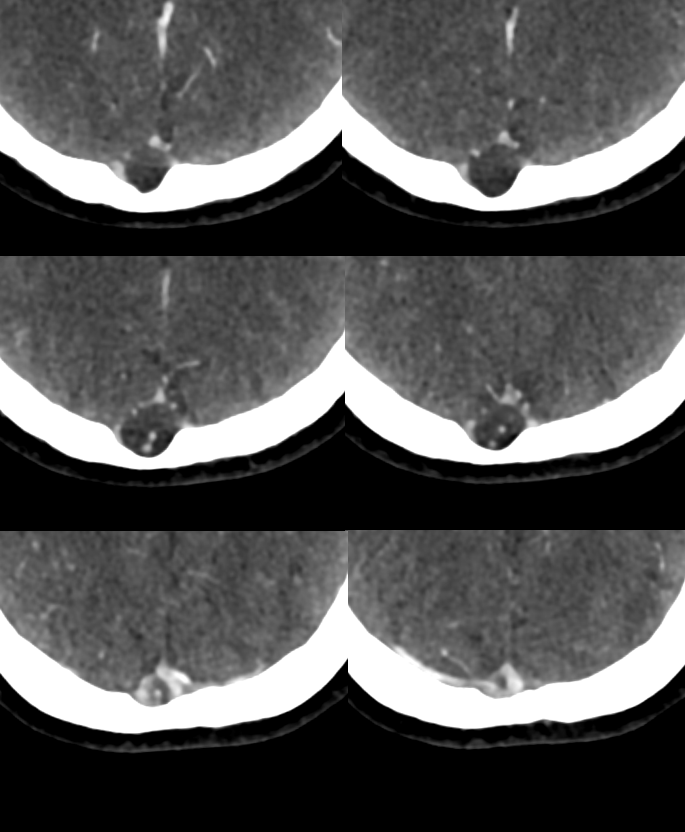

A poorly timed, venous phase CTA shows small caliber of sagital sinus

A poorly timed, venous phase CTA shows small caliber of sagital sinus